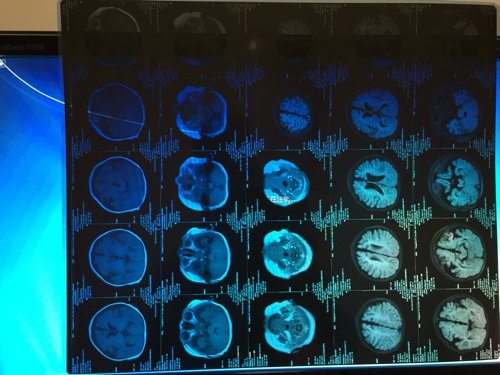

我的宝宝六个月,做核磁提示,脑白质发育不良,两侧额颞部蛛网膜下腔增宽,说明什么?能治好吗? 点击展开 匿名用户 2014-12-03 20:04 为您推荐: 其他回答 宝宝检查看考虑脑发育落后的,目前可注意大运动发育水平,需要积极加营养脑细胞药物,康复训练改善的,主要是避免后遗症的发生。 yh918 2014-12-08 13:39 相关问题 1岁的小孩,坐不稳,不会爬也不会走 做头部核磁显示髓鞘未完全发育的可能性大,双侧额顶颞部蛛网膜下腔 35周早产,在保温箱里呆了13天了,喝奶能喝35ml了,做核磁医生说脑白质少,出生时出现过窒息,让打一周的脑营养针,这针不打可以吗,有必要吗 宝宝早产两个月,住保温箱两个月核磁显示脑白质软化,现在年龄